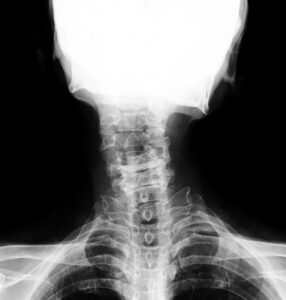

交通事故で最も多い「むち打ち(頸椎捻挫)」を例に、体の中で何が起きているのかを見ていきましょう。

首の骨は、重い頭を支える細い支柱のようなものです。事故の衝撃で首が大きくしなり、筋肉だけでなく、骨と骨を繋ぐ**靭帯(ついかんばん)や、クッションの役割をする椎間板(ついかんばん)**が目に見えないほどの微細な損傷を受けます 。 これにより、腕へとつながる神経が圧迫され、手のしびれや頭痛、めまいといった症状を引き起こすことが分かっています 。